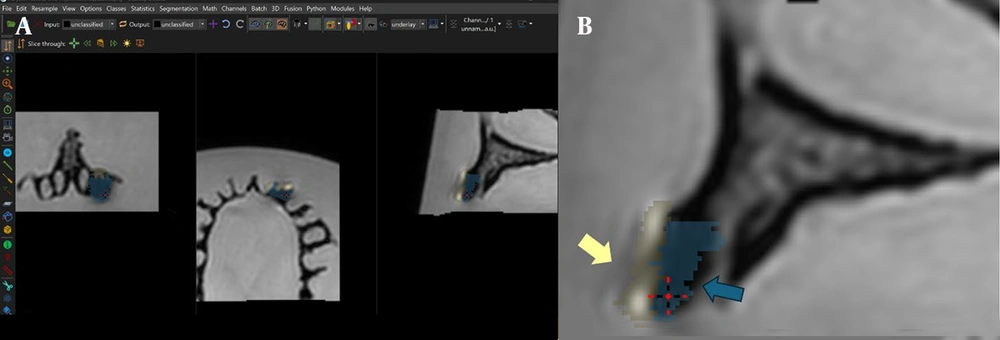

The MRI datasets in DICOM format were imported into Imalytics Preclinical software (Gremse-IT GmbH, Aachen, Germany) (6) for quantitative analysis. An oral and maxillofacial radiologist, trained by a general radiologist and an MRI physicist in artifact recognition and classification, performed all image interpretations. Each measurement was repeated three times at two-week intervals, resulting in an excellent intra-class correlation coefficient (ICC).

All analyses were conducted with the observer blinded to implant material and MRI sequence. Fixed thresholds were applied for both artifact types, and window/level settings (brightness and contrast) were kept constant across all images. To minimize partial-volume effects, boundary voxels at implant margins were excluded from artifact volume calculations. Two artifact types were defined within the software: Signal loss and pile-up artifacts, each assigned a unique color. Signal loss artifacts appeared as dark, signal void regions surrounding the implant, whereas pile-up artifacts were bright regions, often near implant edges, caused by improper image reconstruction, leading to misleading high-intensity signals (14).

Artifact volumes were measured in all three imaging planes (axial, coronal, sagittal) to ensure comprehensive coverage (Figure 4).

Imalytics software environment used for artifact quantification: A, Software interface showing artifact classification in axial, coronal, and sagittal planes; and B, Zoomed-in view of the classified regions, with pile-up indicated by yellow arrows and signal loss indicated by blue arrows. The ‘Statistics’ tab displays corresponding artifact volumes (mm3).

Volumes, calculated in cubic millimeters using the software’s “Statistics” tab, were reported separately for signal loss and pile-up artifacts. For signal loss, the implant volume was subtracted from the total segmented volume (15), while pile-up volumes were directly obtained from the segmented regions. Manual delineation of affected areas was performed slice by slice to maximize precision. Examples from the T2W sequence are shown in Figures 5. and 6.